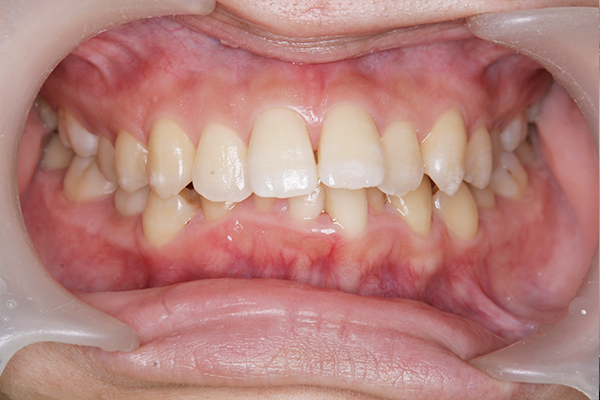

術前

術後

オフィスホワイトニング 38,500円

主訴 歯の色が気になると来院。

全体クリーニング後、1回の施術で効果を実感でき、3回目で希望の白さに近づけた。

治療期間:1日(写真は1回目の処置後)

副作用・リスク:一時的に知覚過敏の症状が出る可能性あり